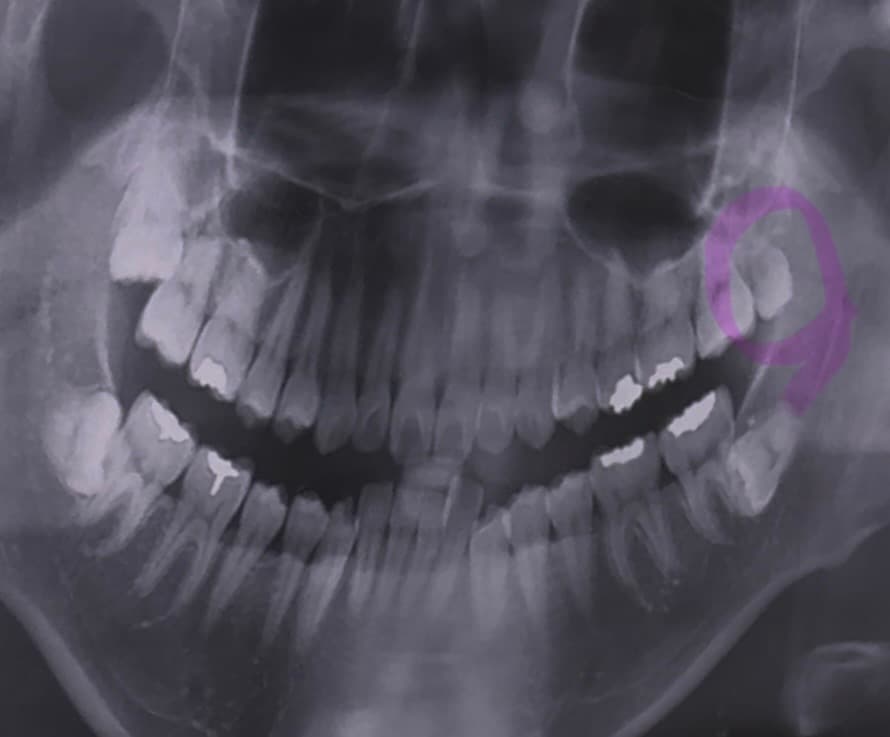

병원에서 윗쪽에 표시한 사랑니에 충치가 있다고 하는데 그냥 뽑는게 맞나요?

반듯하게 난건 나중에 스페어로 쓸수있다 그래서 고민이에요...

• 1번 째 사진